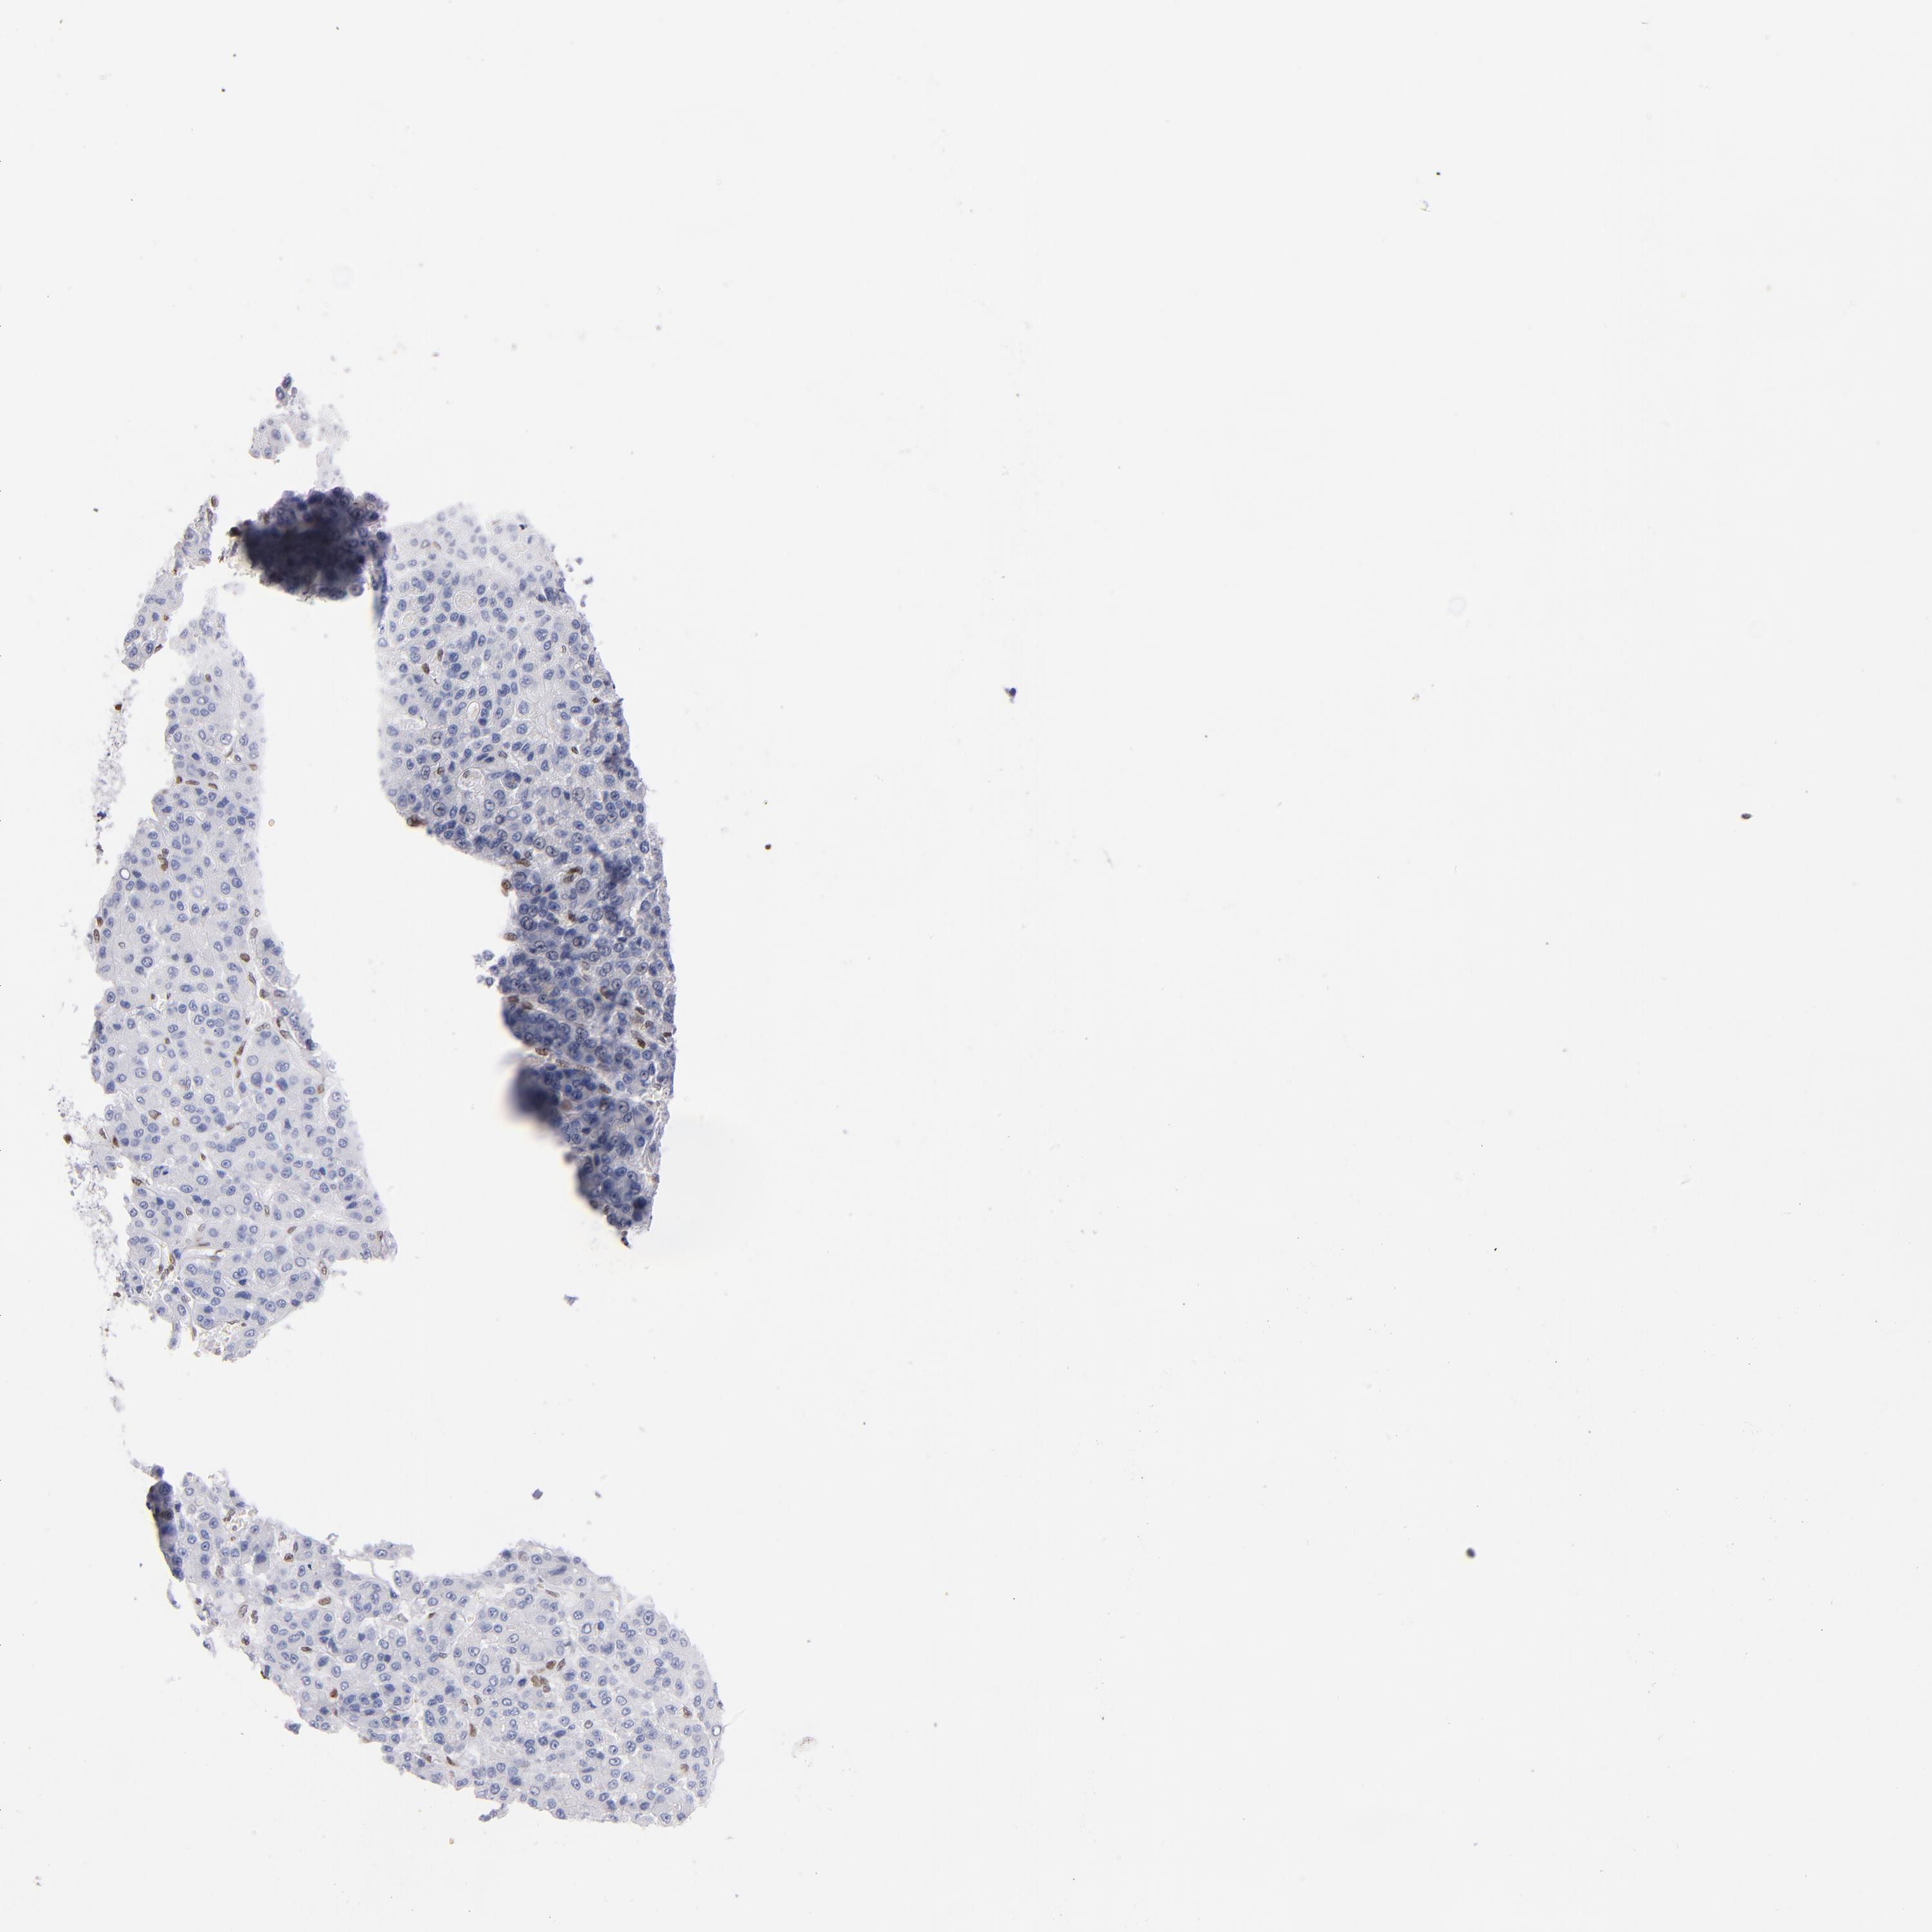

LIVER CANCER - Protein expressioni

A mouse-over function shows sample information and annotation data. Click on an image to view it in a full screen mode. Samples can be filtered based on level of antibody staining by selecting one or several of the following categories: high, medium, low and not detected. The assay and annotation is described here.

Note that samples used for immunohistochemistry by the Human Protein Atlas do not correspond to samples in the TCGA dataset.

Antibody stainingi

Antibody staining in the annotated cell types in the current human tissue is reported as not detected, low, medium, or high, based on conventional immunohistochemistry profiling in selected tissues. This score is based on the combination of the staining intensity and fraction of stained cells.

Each image is clickable and will lead to virtual microscopy that enables deeper exploration of all samples and also displays staining intensity scores, fraction scores and subcellular localization as well as patient and tissue information for each sample.

Antibody HPA002134

Antibody CAB016293

Staining

High

Medium

Low

Not detected

Intensity

Strong

Moderate

Weak

Negative

Quantity

>75%

75%-25%

<25%

None

Location

Nuclear

Cytoplasmic/membranous

Cytoplasmic/membranous,nuclear

Cholangiocarcinoma

Carcinoma, Hepatocellular, NOS